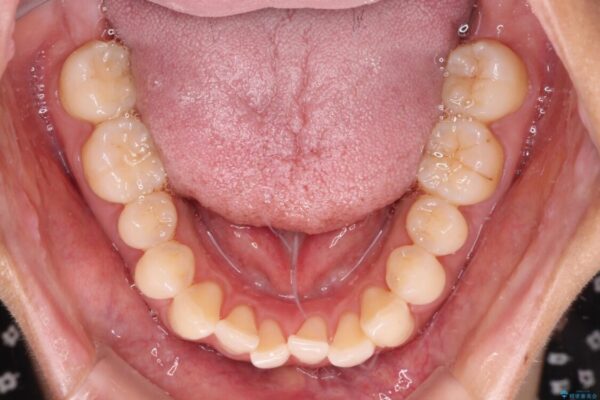

前歯のデコボコで前方に出ていることを気にして来院された患者様です。

上顎前歯が捻れて前方に飛び出しており、下顎前歯もそれに沿うようにデコボコとなっていました。

IPR(歯と歯の間を削る処置)によりスペースを獲得して上下顎前歯のデコボコを改善し、飛び出している前歯が引っ込むように設定し、インビザラインにて矯正治療を行うこととしました。

• 【モニター】前歯のデコボコをインビザラインで改善 治療前画像